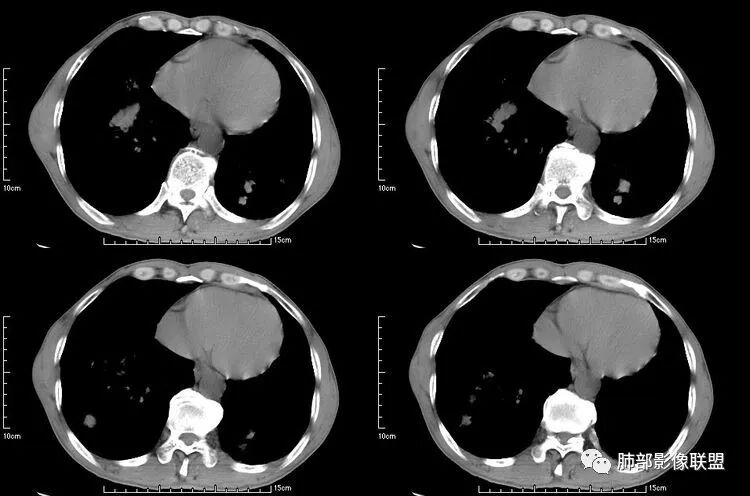

左肺下叶团块病灶,有明显张力,增强后病灶内部有可疑延迟强化,看不清楚病灶与支气管的关系,应该支气管受压阻塞了,双肺多发胸膜下小结节,病灶小结节病灶有平行胸膜生长的表现,部分小结节厚壁,部分薄壁,,还有一部分有内容物,这需要两元论,左肺下叶肺癌(腺癌)伴转移,同时合并真菌感染。

液化,而不像坏死,是有强化的;这个里面似有液平。说明里面有分泌粘液?

这些病灶收缩力,确实不太支持鳞癌的转移。反而,里面是薄壁强化,应该是粘液所致

空洞型肺转移瘤成因尚不完全明确, 可能与鳞癌中心角化物排空 、腺癌黏液样退变后黏液排空 、肿瘤血供不足引起坏死 、肿瘤继发脓肿 、化疗等机制有关,其中部分薄壁囊腔样结可能是肿瘤细胞沿着原有的肺大泡或其它囊性结构生长或者肿瘤向小支气管侵犯引起活瓣性阻塞而形成 ,但无一种机制能解释全部现象。空洞或囊腔大小并不反映病情变化, 其临床意义不大, 而瘤灶的数目及大小, 特别是瘤灶实性成分的多少才可能更准确反映病情变化。肺癌形成空洞与其肿瘤本身性质有明显联系,肿瘤分化程度差,倍增时间越短,恶性程度越高,组织液化坏死形成空洞倾向越明显;鳞癌空洞偏大,内缘不规则,常易形成X线平片中癌梁样改变与CT中壁结节样改变;而腺癌空洞大小不定,洞内分隔明显,内缘不规则,且较难于形成壁结节等改变;合伴空洞的肿瘤边缘情况也对判断肿瘤性质有帮助。

本病例左肺下叶肿块,有深分叶、毛刺、胸膜牵拉凹陷、支气管截断及纵隔内淋巴结肿大等征象,都均支持病灶为恶性,如腺癌,而且叶间裂的多发结节也提示是腺癌来源可能大;双肺多发结节、肿块,大部分病灶有分叶、毛刺及胸膜凹陷的恶性征象,与原发肿瘤本身的性质有关,所以应该与左肺下叶肿块同源,而且双肺多发病灶内空洞也具有多样性;